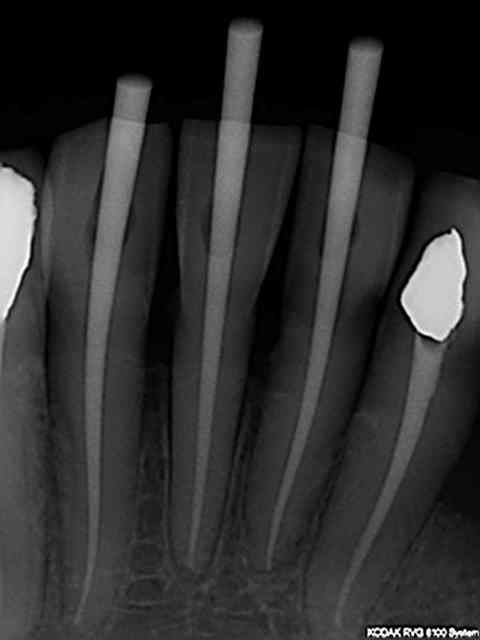

Reciproc ce soir pour reprise endo ( 3 ème utilisation).

Effectivement la progression ne fonctionne que lorsque le canal est perméable, d'où ma question :

Comment faites vous pour désobturer vos canaux ?

- lime manuelle coupée 2O jaune

- lime rotation continue dédiée

J' ai cassé une MTWO reprise bague rouge et bleue ! Pas bien !

Toujours le même problème, forcé pour aller plus loin ou rester ZEN au risque de ne pas réaliser une reprise correcte.

Et vous ?

@Chicot29 : tu désobtures avec la mtwo rouge 7% ?

car je pensais que la R25 pouvait progresser spontanément.

RTE avec le R25 évidemment si c'est obturé avec de la résine sans cone ......

Un coup de s1 protaper si il bloque ce qui arrive si le diamètre du canal est trop fin.